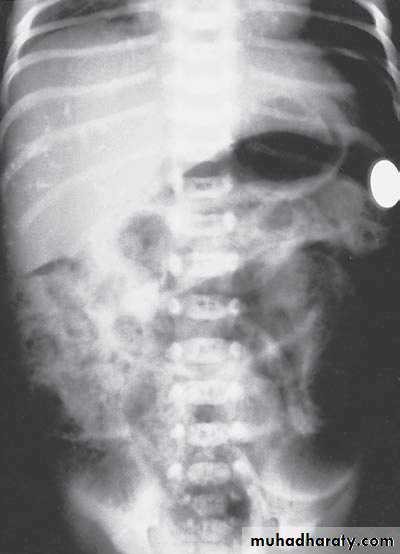

Second photo:

Diagnosis: congenital diaphragmatic hernia

Description: more dextrocardia – diaphragm not present – there is nasogastric tube

severe distress – very tired - 1 day age baby – more number of intestinal loops in

the chest - there is no lung tissue in the chest.

Treatment: pull the intestine ad close the hernia (through abdominal approach).